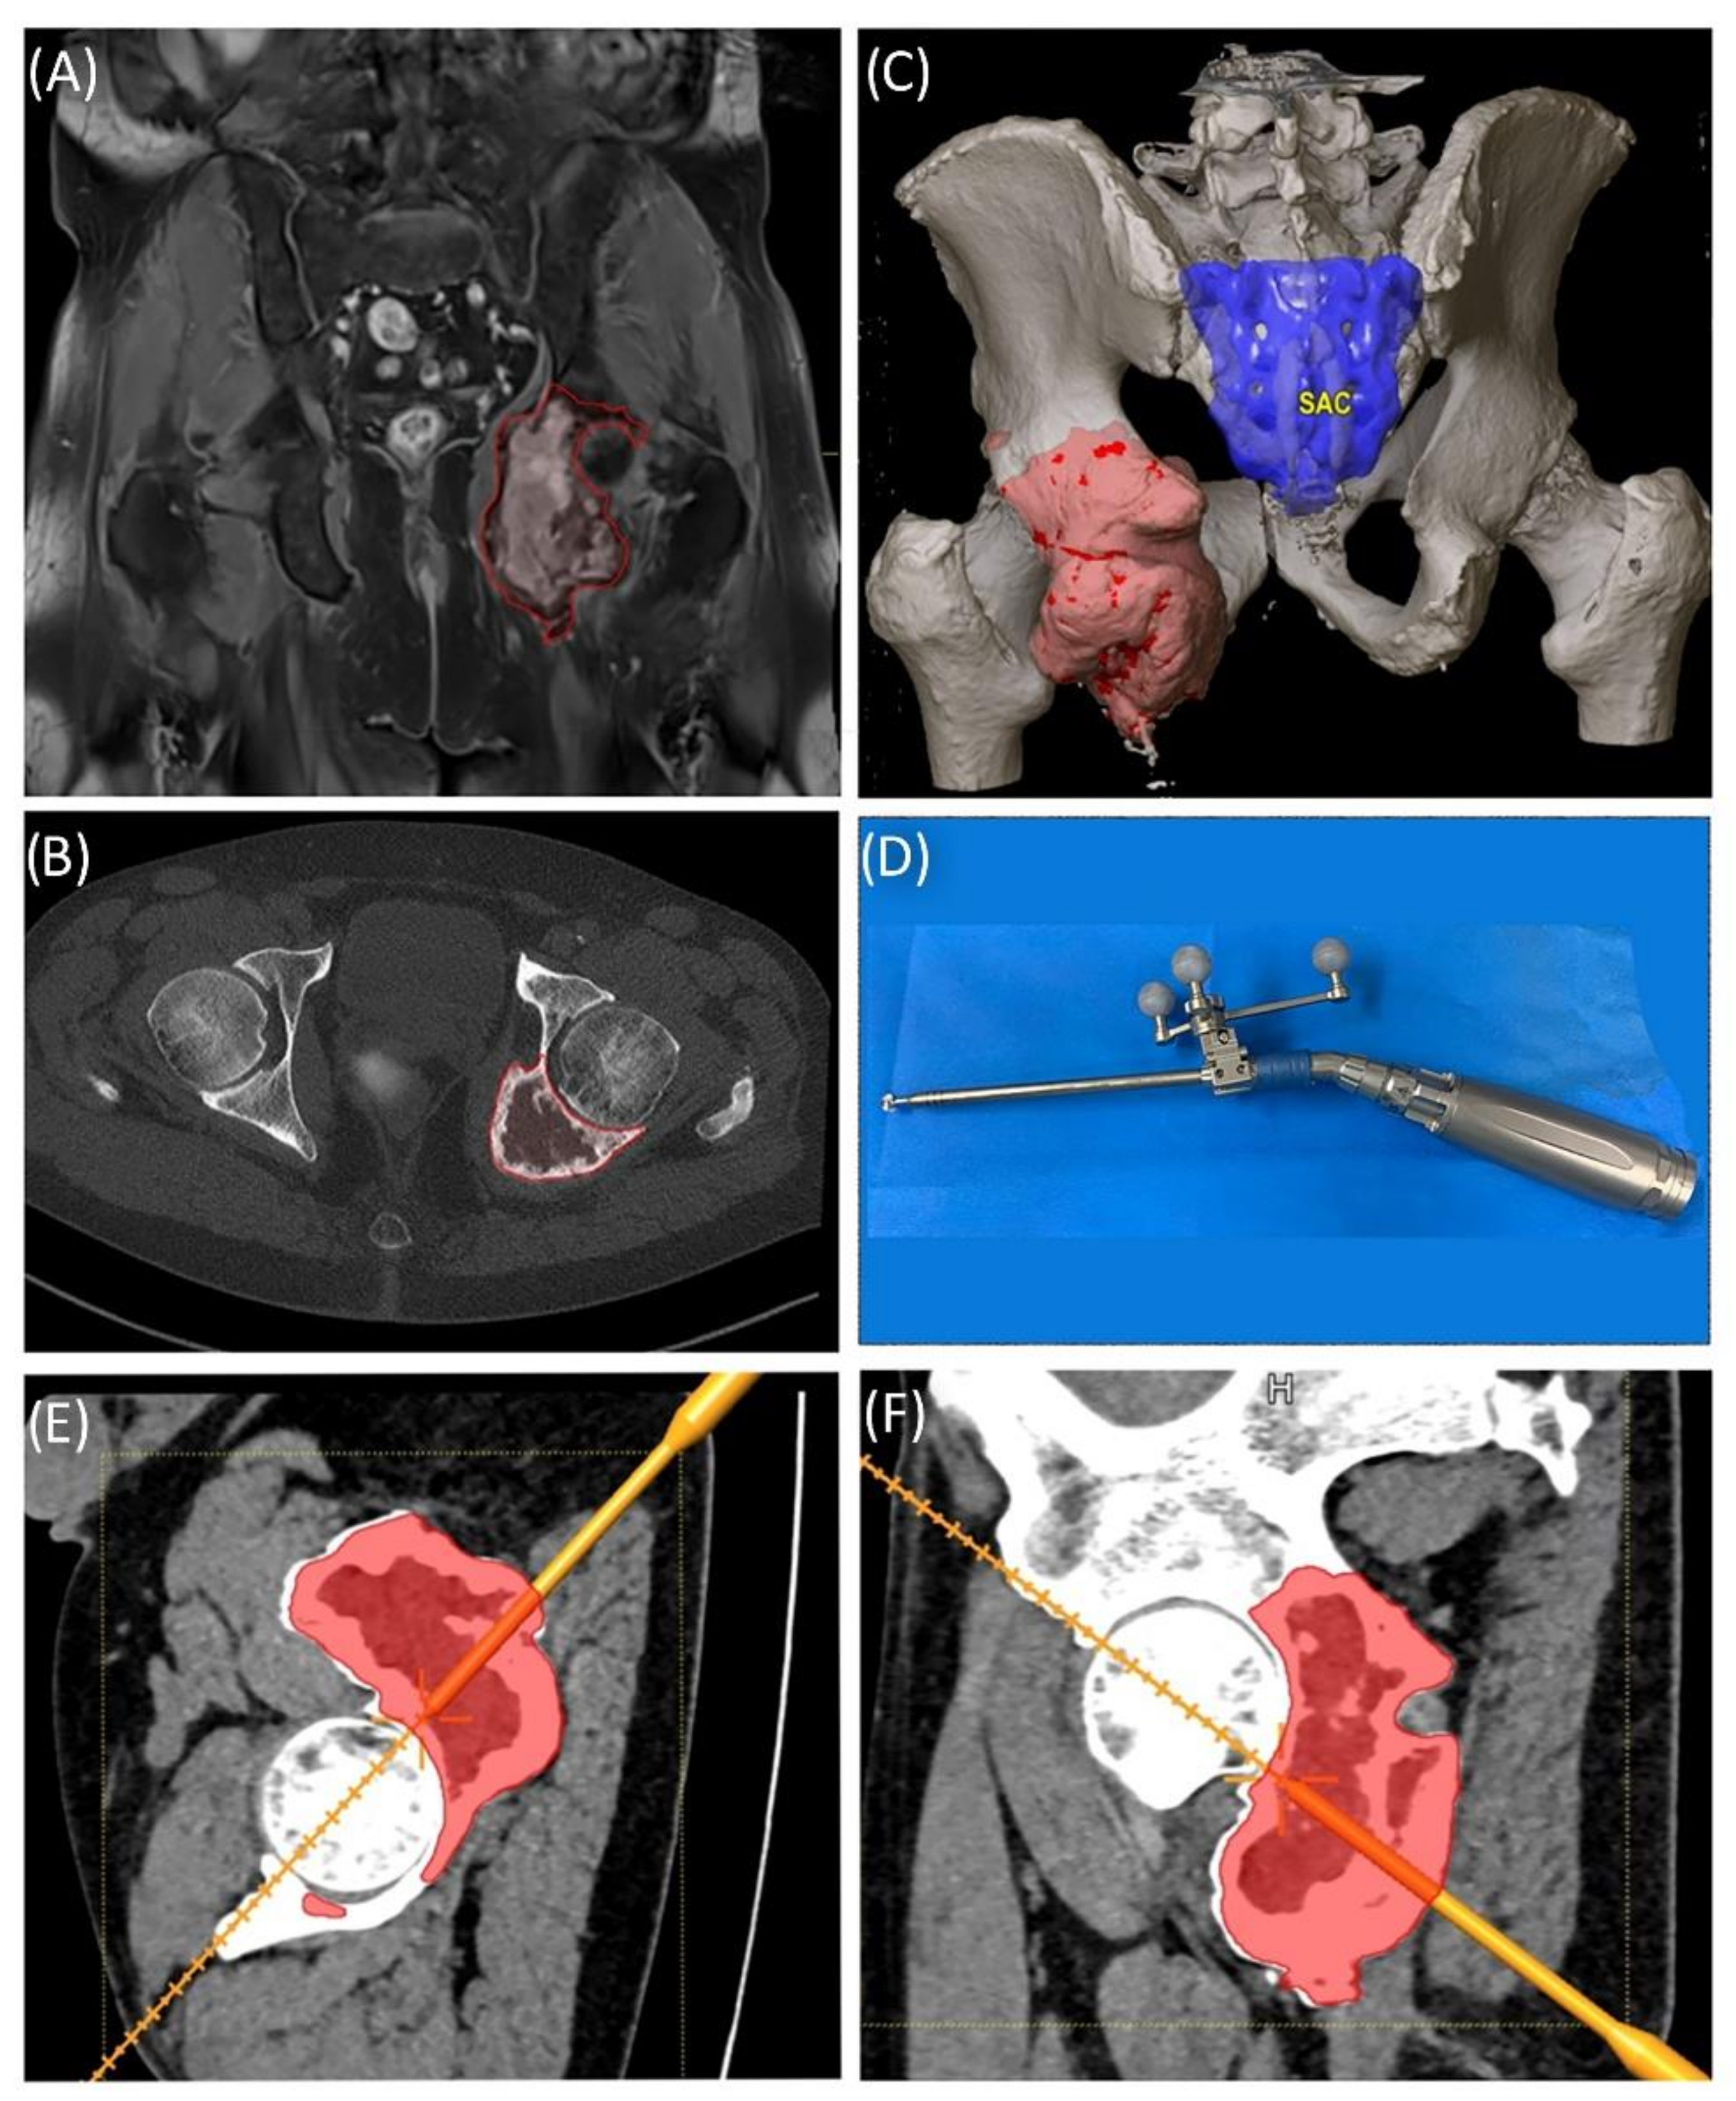

Case 1 involved a 22-year-old female patient suffering from a multiple cartilaginous exostosis disease with a secondary peripheral chondrosarcoma G3 of the right ilium without metastasis. The resection was performed as navigated internal hemipelvectomy (P1a), followed by augmentation of the right ileum with a standard screw-rod system (Expedium, DePuy Synthes Spine Inc., Raynham, MA, USA) and revision cement (COPAL® G+C, Heraeus, Wehrheim, Germany) (Figure 2). This procedure allowed preservation of the hip joint. Trochanter resection was followed by reconstruction of the ventral hip joint capsule and reinsertion of the musculature using an attachment tube (Implantcast, Buxtehude, Germany). During treatment, superficial dry skin necrosis at the Enneking approach site occurred without signs of infection and eventually healed. The first follow-up 3 months after surgery showed a stable and increasingly fluid gait pattern with a positive Trendelenburg sign. The range of motion of the right hip joint was fully preserved. At the 15-month follow-up, the patient was free of pain and was able to walk a three-kilometer distance. The native X-ray and MRI of the pelvis showed no signs of tumor recurrence.

Figure 2. Case 1: Preoperative planning and segmentation of tumor volume components [bony (pink) and soft tissue (teal)] (A); resection planes [transverse (orange) and axial (blue)] during surgery with navigated chisel (orange) (BE) intraoperative situs during resection (F); postoperative radiograph with reconstructed iliac defect (G).